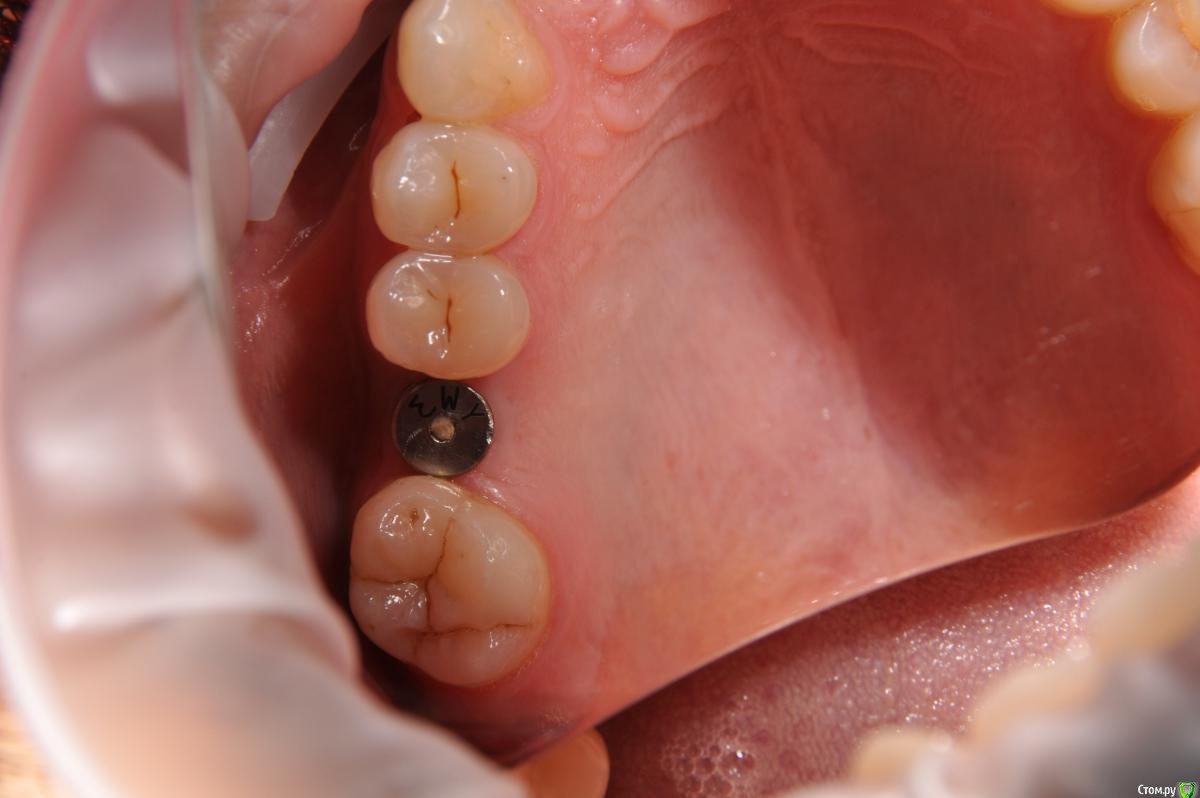

kamranchick Опубликовано 12 сентября, 2018 Автор Поделиться Опубликовано 12 сентября, 2018 Вот) Ссылка на комментарий

Евгений Ходыкин Опубликовано 12 сентября, 2018 Поделиться Опубликовано 12 сентября, 2018 Нуу...в общем... сам всё понимаешь))) Ссылка на комментарий

kamranchick Опубликовано 12 сентября, 2018 Автор Поделиться Опубликовано 12 сентября, 2018 Нуу...в общем... сам всё понимаешь))) что лучше ходить с формиком?)) Ссылка на комментарий